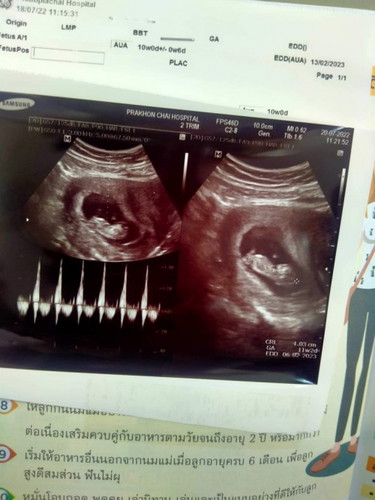

ของเราไม่รู้สึกว่าดิ้นนะคะเพราะหน้าท้องหน้าแต่พอไปอัลตร้าซาวเท่านั้นและดิ้นใหญ่เลย น้อง11สัปดาห์ค่ะ